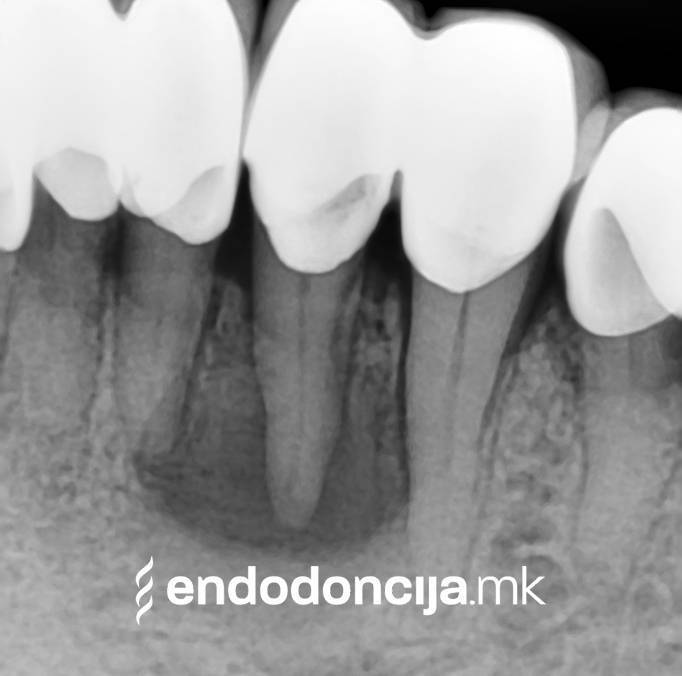

Με τη σωστή θεραπεία, όχι μόνο οι οξείες φλεγμονές αλλά και οι χρόνιες μπορούν επίσης να αντιμετωπιστούν με επιτυχία. Αυτά μπορεί να προκαλέσουν πόνο ή μερικές φορές ακόμη και εντελώς χωρίς συμπτώματα. Η έγκαιρη ανίχνευση και εξάλειψη τέτοιων φλεγμονών είναι ζωτικής σημασίας για τη μακροχρόνια συντήρηση των δοντιών.

Οι υπηρεσίες του Ειδικού Τμήματος Ενδοδοντικής δεν περιορίζονται καθόλου στη συμβατική επεξεργασία ριζικών καναλιών. Αντιμετωπίζουμε αποκλειστικά τους ασθενείς μας με τα νεότερα υλικά και όργανα με μικροσκόπιο, προκειμένου να είμαστε σε θέση να καθαρίσουμε εντελώς και να προετοιμάσουμε όλα τα κανάλια πριν τα γεμίσουμε.